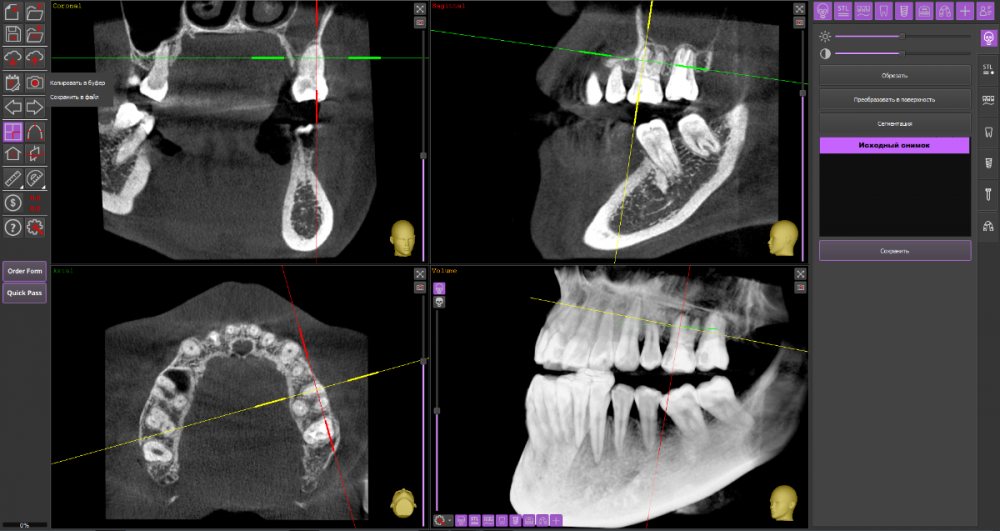

Киста 6,7 слева и гайморит

Зубы: лечение начала в конце декабря. на кт обнаружили кисту над 6,7 зубами слева. 7 зуб заходит в пазуху. Начали лечить 6, сказали что попробуют спасти, заложили лекарство на 2 недели. Также стоял ортодонтический имплантат рядом с 7 зубом, сказали что находится очень близко к корню зуба и пазухе. Имплант удалили.

4. хирург лор сказал что если вырывать зубы то он за одну операцию вырвет зубы и поставит импланты

КТ

Думаю, стоит пока попробовать консервативное лечение у стоматолога-терапевта.

27_2.thumb.png.af0bfed3f3a1dd81e321fdeb61e4984b.png

@wladdX Подскажите пожалуйста, а какие риски могут быть? Правда что у меня там нижняя стенка пазухи истончается изза воспаления ?